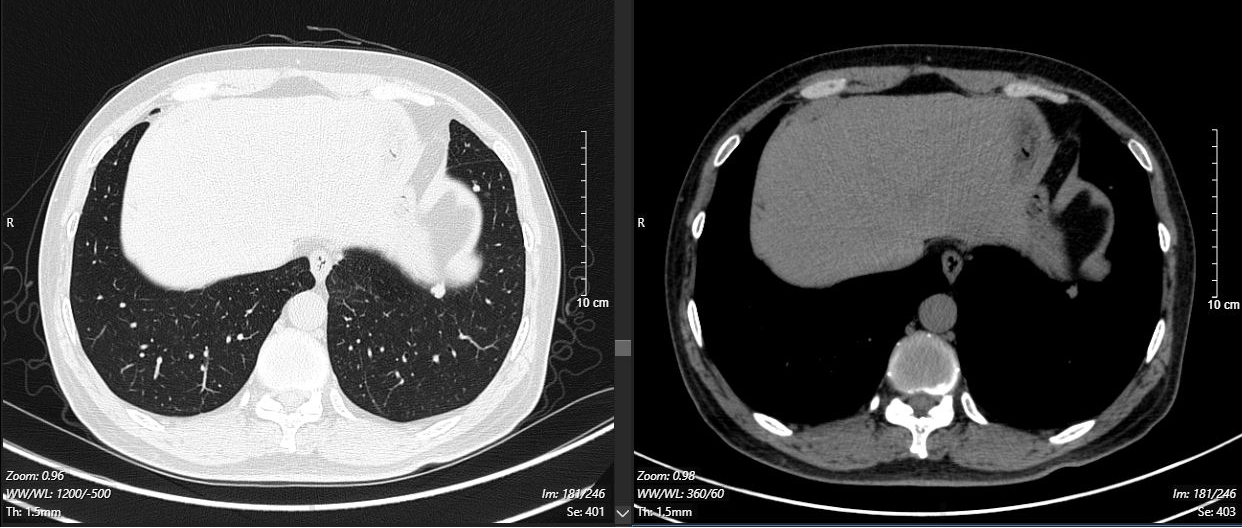

现病史:2024-11-18外院体检时行胸部增强CT示:两肺纹理增多,左肺下叶软组织密度影,大小约3.7*3.1cm,边缘见少许毛刺影,周围见少许斑片模糊影,左肺见多发结节影,最大径约9mm。左肺下叶占位,考虑肺癌,请结合纤维支气管镜及生化检查。左肺多发结节,肺内转移不排除。

2024-11-26 胸部CT检查示:

2024-11-26 PET-CT进一步评估:左肺下叶背段近肺门处类圆形分叶状肿块(约32*28mm),FDG代谢异常增高;纵隔内4L组、左下肺门处、左侧膈肌脚内侧见稍大淋巴结FDG代谢增高,左肺内及胸膜下散在多发结节影,FDG代谢不同程度增高,考虑左肺下叶肺癌伴左肺及胸膜多发转移、多发淋巴结转移。

治疗5个月后(2025-05-07):复查CT显示左肺病灶显著缩小,达到PR,肺内结节明显吸收。